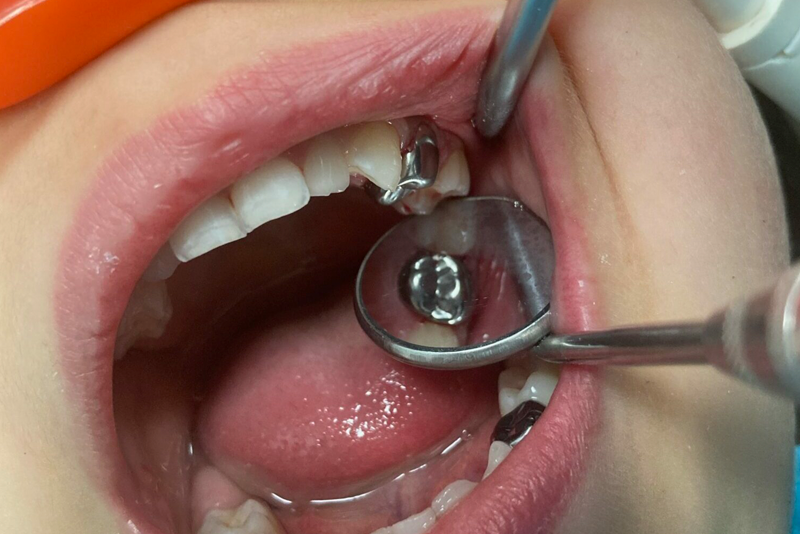

3. CHỤP THÉP CÓ SẴN: GIẢI PHÁP TỐI ƯU CHO RĂNG SỮA

Khi trẻ em bị sâu răng, các tổn thương có thể diễn ra rất nhanh chóng và nghiêm trọng. Lớp men và ngà răng của trẻ thường mỏng hơn, độ khoáng hóa thấp hơn và khả năng tự chăm sóc răng miệng của trẻ cũng hạn chế. Đối với những tổn thương sâu đơn giản, phương pháp hàn cổ điển có thể được áp dụng. Tuy nhiên, trong trường hợp sâu răng nặng gây vỡ lớn thân răng, cần thực hiện nhiều thủ thuật điều trị phức tạp, bao gồm cả điều trị tủy và lắp chụp răng.

LỢI ÍCH CỦA CHỤP THÉP CÓ SẴN

Chụp thép có sẵn được coi là một trong những phương pháp phục hồi hiệu quả nhất cho răng hàm sữa và răng hàm vĩnh viễn. Những ưu điểm nổi bật của chụp thép bao gồm:

- Độ Bền Cao: Chụp thép có khả năng chịu lực tốt, giúp trẻ có thể ăn nhai thoải mái.

- Bảo Vệ và Hỗ Trợ Tốt: Chụp thép vừa bảo vệ cho thân răng, vừa giúp duy trì khả năng nhai và phát âm cho trẻ.

- Tiện Lợi Trong Điều Trị: Quá trình lắp đặt chụp thép nhanh chóng và dễ dàng, giảm thiểu thời gian điều trị cho trẻ.

- Cảm Giác Thoải Mái: Nhờ thiết kế mỏng, chụp thép không chỉ phù hợp với cấu trúc răng của trẻ mà còn tạo cảm giác dễ chịu khi sử dụng.

Dù có những lo ngại về mặt thẩm mỹ do màu bạc của chụp thép, nhưng thực tế chụp thép được làm từ hợp kim thép không gỉ, an toàn cho sức khỏe. Loại vật liệu này đã trải qua nhiều nghiên cứu và cải tiến để đạt được độ bền và hiệu quả tối ưu trong điều trị.

Chụp thép có sẵn, giải pháp tối ưu cho bảo vệ răng sữa